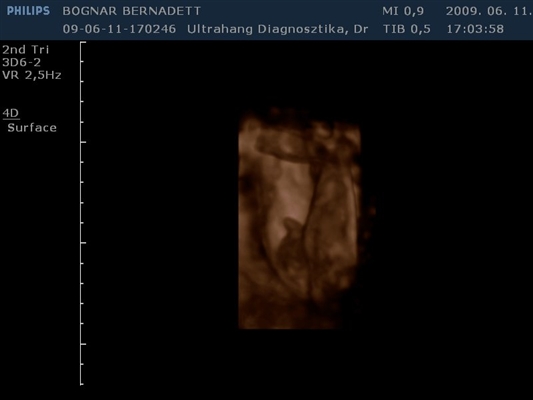

Kb. 3,5 hete én is voltam 4D-n és egy egész jó kis kép kerekedett belőle, majd felteszem.